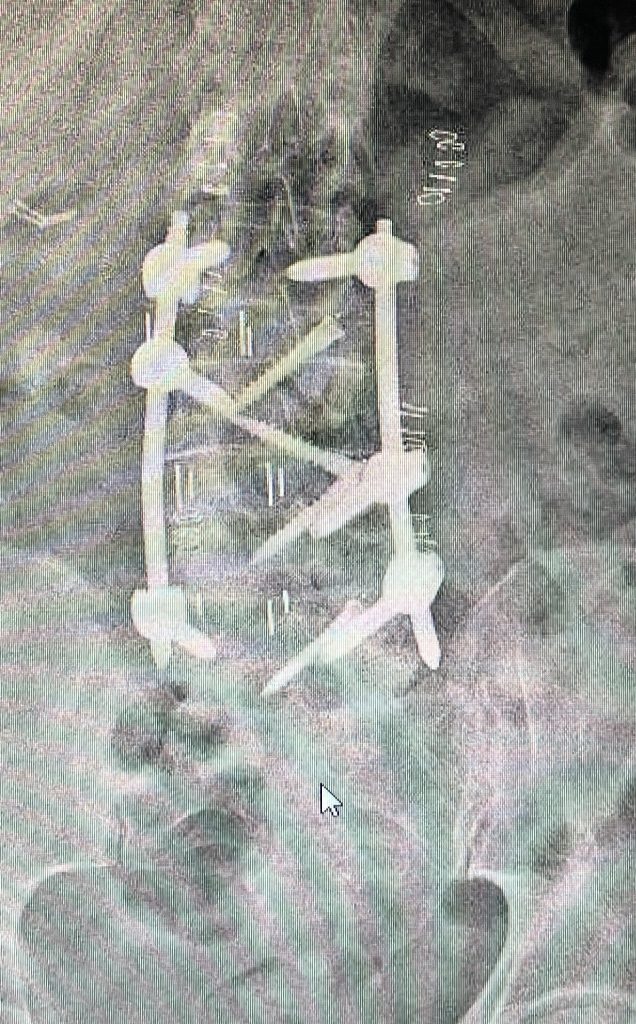

Existen múltiples técnicas para conseguir la fusión de la columna lumbar. La artrodesis posterior instrumentada es la técnica más habitual. Consiste en colocar tornillos de fijación en las vértebras, y un implante a nivel del disco (caja intervertebral), lo que permite liberar nervios en el canal espinal y reconstruir la columna de un modo muy efectivo. La técnica habitual se denomina TLIF (transforaminal lumbar interbody fusion). Esta técnica también puede realizarse de forma mínimamente invasiva.

Esta técnica permite en pacientes seleccionados respectar la musculatura lumbar y acortando los tiempos de recuperación.Finalmente, esta fusión se puede realizar de manera mínimamente invasiva, con una pequeña incisión a través del lateral del abdomen, lo que se denomina técnica XLIF u OLIF (extrem lateral lumbar interbody fusion).Técnica mínimamente invasiva, utilizada para favorecer la reconstrucción vertebral y fusión en deformidad y casos con afectación de múltiples discos.